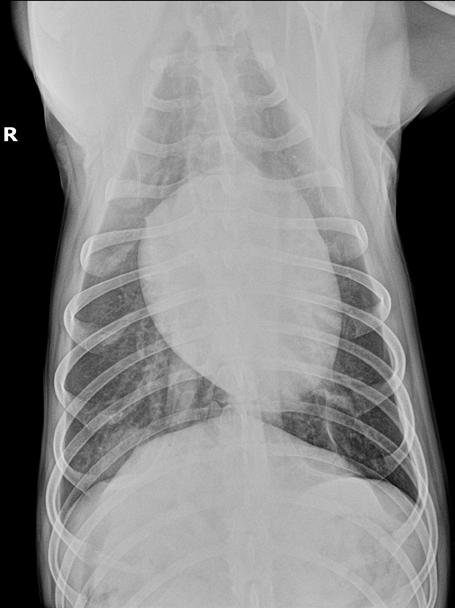

Se presenta un labrador hembra esterilizada de 6 años a mediados del mes de agosto en la región de Madrid, con historial de fiebres recurrentes de 15 días de evolución a la cual se le realizaron pruebas de enfermedades infecciosas transmitidas por vectores (Ehrlichia, Anaplasma, Filaria y Leishmania) con resultados negativos. Se administró antibioterapia de amplio espectro y antiinflamatorios no esteroideos y las fiebres cesaron puntualmente. Su centro veterinario la remitió porque al terminar el tratamiento la paciente volvió a mostrar decaimiento y fiebre de 39,7 ºC. Analíticamente presentaba leucocitosis neutrofílica severa (30,96 x 109/l; RR: 6,00-17,00 x 109/l) y un panel bioquímico sin alteraciones reseñables. Se realizó proteína C reactiva con valor superior a 150 mg/dl (RR: 1-10 mg/dl). Se realizó estudio ecográfico abdominal que no presentaba alteraciones. Se realizó un estudio radiográfico de tórax con proyecciones lateral derecha y ventrodorsal (Fig. 1).

Figura 1. Radiografías de tórax de la paciente en proyección lateral derecha (A) y ventrodorsal (B). Fallo en la técnica: Presencia de la letra indicativa del decúbito en superposición con la paciente.

En la proyección lateral derecha se evidencia un patrón intersticial no estructurado en el aspecto dorsal de los lóbulos pulmonares caudodorsales que impide la correcta visualización del pilar diafragmático derecho a dicho nivel; en este caso, la proyección presenta una rotación significativa la cual posiblemente haya permitido visualizar la lesión radiológica con mayor claridad (Fig. 2A). Asimismo, en la proyección ventrodorsal se localiza en la zona de proyección del lóbulo pulmonar caudal derecho un foco de patrón intersticial no estructurado junto a una lesión de tipo nodular y bordes mal definidos, en la zona de proyección de la décima costilla (Fig. 2B). Se observa, además, la presencia de fisuras pleurales, indicativas de efusión pleural leve bilateral. El resto de las estructuras evaluables no muestran alteraciones reseñables.

Diagnósticos compatibles con los signos radiográficos observados (diagnóstico diferencial) Los hallazgos observados incluyen un patrón intersticial no estructurado con interrupción del pilar diafragmático derecho, junto con un patrón estructurado de tipo nodular de 25 x 54 mm, ambos localizados en la porción caudodorsal del lóbulo pulmonar caudal derecho. Estos hallazgos sugieren los siguientes diagnósticos diferenciales: absceso/granuloma pulmonar, tromboembolismos pulmonares, tumores pulmonares

primarios (carcinoma broncoalveolar, adenocarcinoma pulmonar, sarcoma histiocítico, carcinoma de células escamosas.), metástasis únicas de tumores primarios o un área única de consolidación pulmonar simulando un nódulo debido a una neumonía o bronconeumonía. Además, las fisuras pleurales indican la presencia de efusión en el espacio pleural, la cual puede ser de tipo trasudado puro (p. ej., hipoproteinemia), trasudado modificado (p. ej., neoplasias pulmonares/pleurales, quilotórax, trauma torácico), exudado (p. ej., piotórax) o de tipo hemorrágico.

(A) Radiografía de tórax en proyección latero-lateral

resaltado se observa un patrón intersticial no estructurado a nivel caudodorsal (círculo) que impide la correcta visualización del pilar diafragmático derecho. Además, se evidencia la presencia de fisuras pleurales (flechas). (B): Radiografía de tórax en proyección ventrodorsal; resaltado se evidencia un patrón estructurado de tipo nodular en la zona de proyección de la décima costilla (círculo).

Figura 2. Mismas radiografías

Figura 1.

derecha;